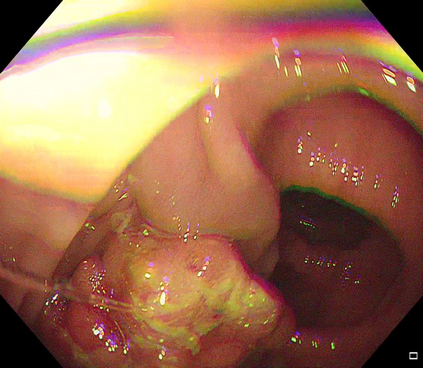

Polyps are early cancer indicators, so assessing occurrences of polyps and their removal is critical. They are observed through a colonoscopy screening procedure that generates a stream of video frames. Segmenting polyps in their natural video screening procedure has several challenges, such as the co-existence of imaging artefacts, motion blur, and floating debris. Most existing polyp segmentation algorithms are developed on curated still image datasets that do not represent real-world colonoscopy. Their performance often degrades on video data. We propose a video polyp segmentation method that performs self-supervised learning as an auxiliary task and a spatial-temporal self-attention mechanism for improved representation learning. Our end-to-end configuration and joint optimisation of losses enable the network to learn more discriminative contextual features in videos. Our experimental results demonstrate an improvement with respect to several state-of-the-art (SOTA) methods. Our ablation study also confirms that the choice of the proposed joint end-to-end training improves network accuracy by over 3% and nearly 10% on both the Dice similarity coefficient and intersection-over-union compared to the recently proposed method PNS+ and Polyp-PVT, respectively. Results on previously unseen video data indicate that the proposed method generalises.